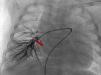

Realizou cateterismo diagnóstico e terapêutico aos cinco meses: pressões sistémicas e pulmonares normais; angiografia na artéria pulmonar: ramos de bom calibre e retorno venoso normal (perfusão mista do campo inferior direito vinda da artéria pulmonar e MAPCA) (Figura 2); angiografia na aorta: colateral larga (7 mm), origem no tronco celíaco, dirigindo‐se para o pulmão inferior direito (Figura 3). Decidida embolização da colateral com Amplatzer (10‐7 PLUG II), ficando com shunt residual (Figura 4).